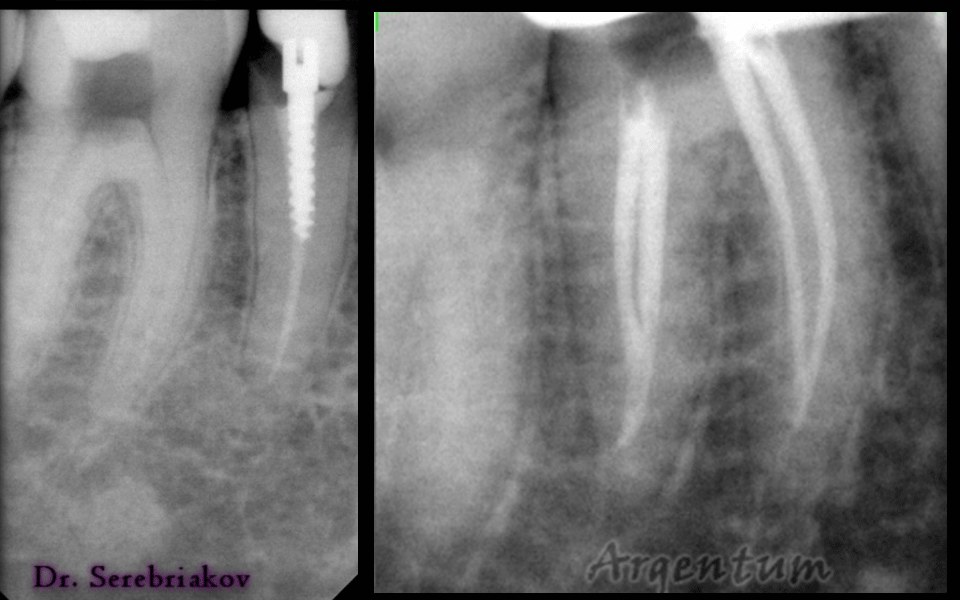

Узкий, извилистый со множеством ответвлений — так можно охарактеризовать канал зуба. Вычистить канал от инфекции и качественно запломбировать зубной канал — основная задача врача эндодонтиста — микроскописта. Корневой канал будет вычищен и запломбирован на 100%. Воспаление в зубе возникает из-за опасных бактерий и на первом этапе врач вычищает корневой канал, делает его стерильным и готовым к пломбированию. Корневой канал узок (в диаметре меньше миллиметра) и имеет множество ответвлений, поэтому пройти его на ощупь чрезвычайно сложно, а вот с применением микроскопа возможно. Прежде всего, врач видит что делает! Все устья и ответвления в канале врач видит, а не определяет на ощупь! При 40 кратном увеличении врач эдодонт качественно подготавливает канал к пломбировке, ликвидирует все очаги возможного воспаления. На следующем этапе врач качественно запломбирует канал горячей гутаперчей – самым современным надежным на сегодняшний день внутриканальным пломбировочным материалом. Как только Вы почувствовали зубную боль — немедленно обращайтесь к врачу стоматологу, не дожидайтесь воспаления зубных каналов и ночной боли.

Установленная под микроскопом пломба простоит в 2 раза дольше, ведь врач под увеличением проверит качество прилегания пломбы к зубу, а значит обеспечит ее герметичность. Любое воспаление под пломбой возникает при нарушении ее герметичности. С применением микроскопа пломба содержит большее количество слоев пломбировочного материала. Под значительным увеличением врач аккуратно слой за слоем восстановит разрушенный зуб повторяя структуру ткани идентично живому зубу, внутри будет более прочный материал для распределения нагрузки, а снаружи более прозрачный для естественной белизны и преломления света. Диагностика кариеса под микроскопом обладает высокой точностью. При помощи микроскопа врач не пропустит начальный кариес, увидит кариес в стадии пятна, обнаружит трещины и сколы. При ранней диагностики кариеса без сверления и без бормашины можно остановить кариес специальными изоляционными пломбировочными материалами. Зубу будет возвращена герметичность, а вы никогда не узнаете, что такое зубная боль.

Ответвления каналов

канал зуба должен быть на 100% очищен от инфекции и запломбирован полностью.

Направление и ход каналов

канал извилист и запломбировать его полностью можно только увидев направление канала зуба.